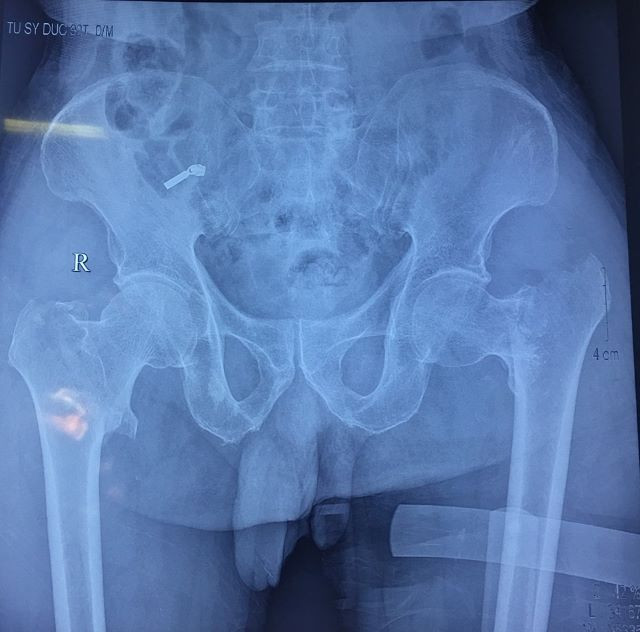

| Hình ảnh phim chụp |